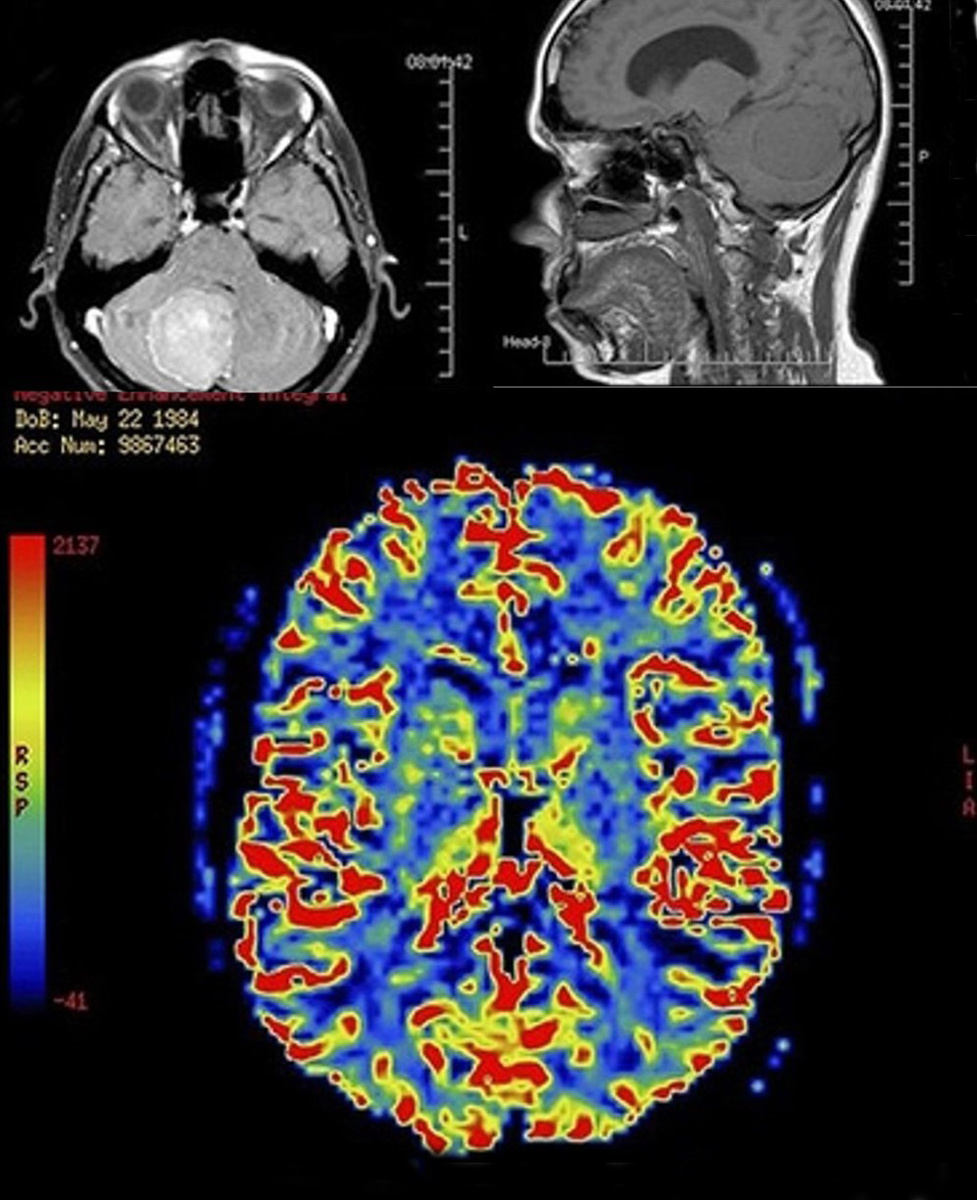

Это мозг. Мозг в МРТ. Сразу скажу не мой. Но согласитесь, мозг в МРТ это красиво. Мне делали. Но я не помню картинку хорошо. Я рассматривала картинку секунд семь и убедившись, что это мне не несет ничего познавательного, тут же утратила интерес. И врач сказал, что все нормально и также потерял интерес. И это хорошо. Плохо, когда государство перестает интересоваться мозгами. Мне кажется картинка на самоим деле должна быть иной. Но я носительница собственной женской логики. А МРТ придуман мужчиной. Армянином (даже талантливым армянином). Но визуализация все равно не совсем наша. Если бы МРТ придумала женщина, то на женском МРТ мозг выглядел бы как-то так: Каким бы выглядел мужской мозг? Тут можно гадать. Это чистая механика, без надежд на восхождение мышления к высшим формам, когда для решения уравнений не важно сколько неизвестных. Решается все. Даже то, что не имеет решения. Оно решается тольк

Это мозг. Мозг в МРТ. Сразу скажу не мой. Но согласитесь, мозг в МРТ это красиво. Мне делали. Но я не помню картинку хорошо. Я рассматривала картинку секунд семь и убедившись, что это мне не несет ничего познавательного, тут же утратила интерес. И врач сказал, что все нормально и также потерял интерес. И это хорошо. Плохо, когда государство перестает интересоваться мозгами. Мне кажется картинка на самоим деле должна быть иной. Но я носительница собственной женской логики. А МРТ придуман мужчиной. Армянином (даже талантливым армянином). Но визуализация все равно не совсем наша. Если бы МРТ придумала женщина, то на женском МРТ мозг выглядел бы как-то так:

Женские мозги. Наши. Красиво. Но ничего не понятно. Но это смотря кому. Тому кто не может отличить малиновый цвет от фуксии  - это никогда не будет понятно.

Женские мозги. Наши. Красиво. Но ничего не понятно. Но это смотря кому. Тому кто не может отличить малиновый цвет от фуксии - это никогда не будет понятно. (но это не точно)